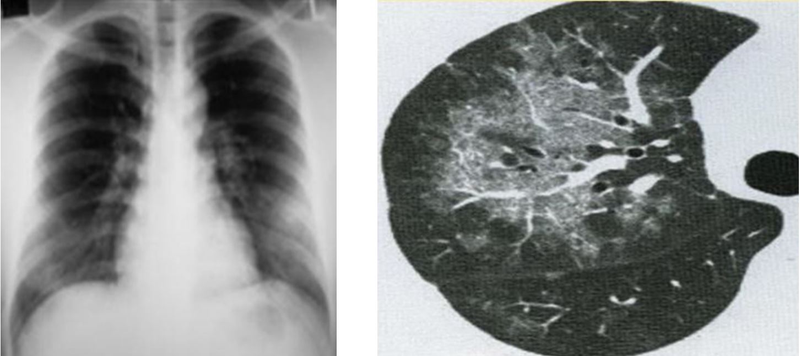

Chụp cắt lớp vi tính phổi, hay còn gọi là chụp CT phổi, là một trong các phương pháp hình ảnh học được sử dụng rộng rãi để đưa ra chẩn đoán và theo dõi điều trị các bệnh lý phổi. Quá trình này liên quan đến việc sử dụng nhiều hình ảnh X-quang chụp từ các góc độ khác nhau, sau đó kết hợp chúng lại để tạo ra hình ảnh cắt ngang và 3D của cấu trúc bên trong màng phổi.

Ngoài ra, việc thực hiện chụp cắt lớp vi tính phổi có thể hữu ích hơn trong việc chẩn đoán khối u phổi so với việc sử dụng chụp X-quang phổi thông thường. Bằng cách này, bác sĩ có thể xác định vị trí, kích thước và hình dạng của khối u phổi, cũng như kiểm tra sự hiện diện của các hạch bạch huyết hoặc dấu hiệu lây lan của tế bào ung thư từ phổi.

Chụp cắt lớp vi tính phổi là một trong những kỹ thuật chẩn đoán hàng đầu cho việc phát hiện các bệnh lý liên quan đến phổi, đặc biệt là khối u phổi. Kỹ thuật này mang lại giá trị chẩn đoán cao bằng cách tạo ra hình ảnh chi tiết và rõ ràng về cấu trúc bên trong phổi, giúp bác sĩ phát hiện sớm các dấu hiệu của khối u phổi, bao gồm cả các khối u lành tính và ác tính.